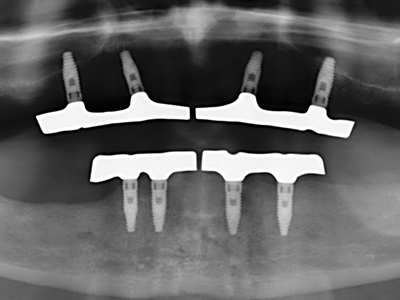

Piezo surgery has additional advantages when harvesting bone blocks. In addition to the high precision with osteotomy described above, the use of the thin saw tips specifically minimizes loss of material. Greater loss of material during harvesting can be expected with the thicker instrument tips, particularly when using Lindemann drills (Lakshmiganthan, Gokulanathan et al. 2012). The basal separation, which is necessary particularly for retromolar block transplants, is simplified by specially designed rectangular saws, with the result that piezo surgery is viewed as a precise, simple and safe procedure for harvesting retromolar bone blocks (Happe 2007) (Fig. 1-12).